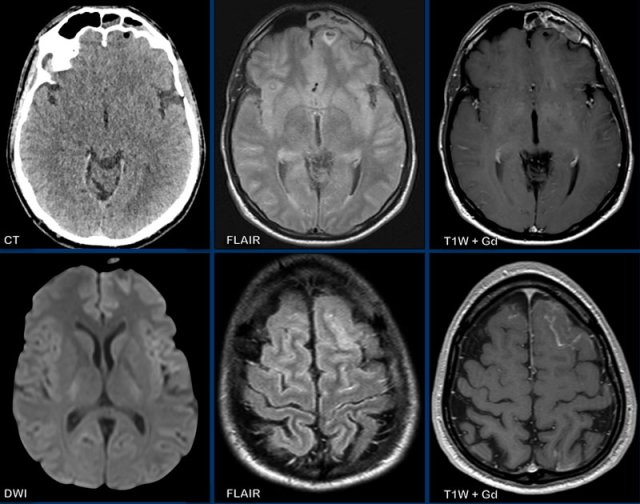

This patient presented with headache.

Images

- CT: notice a small air focus at the left on the left side, with only minor sinus secretions in the left frontal sinus.

- FLAIR: a small hyperintense lesion with a central hypo-intens focus.

- T1W+Gd: no enhancement of the lesion, but only faint leptomeningeal enhancement.

- DWI: no restricted diffusion.

- FLAIR image at a higher level shows hyperintensity in the left frontal subarachnoid space and at the frontal cortex, which is compatible with meningitis.

- T1W+Gd: enhancement in the left frontal subarachnoid space